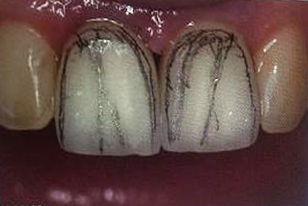

Tehnicile adezive directe de lucru cu materiale bazate pe rasini composite reprezinta o modalitate excelenta de restaurare estetica si minim invaziva a dintilor frontali. Obtinerea rezultatelor estetice asteptate este legata indesolubil de alegerea si utilizarea corecta, conform indicatiilor, a materialelor si tehnicilor de lucru adecvate, fiecarei situatii clinice.